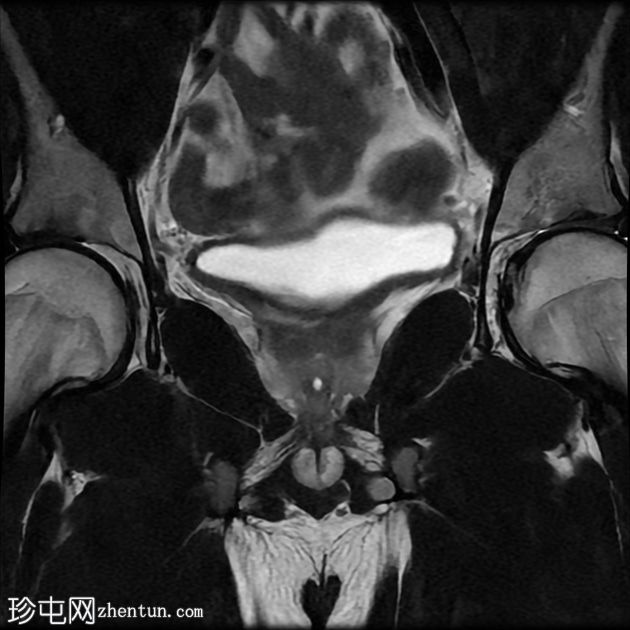

冠状位

T2加权像

前列腺大小为32.8 x 41.5 x 34.7 mm(前后径 x 宽度 x 头尾径),体积为25.88 ml,属于正常范围。前列腺中央可见一逗号状囊性占位性病变,大小为17.3 x 12.1 x 9.3 mm(头尾径 x 前后径 x 宽度)。可见囊肿与前列腺尿道相通。囊内未见可疑内容物——具体而言,未见囊内出血或碎屑——弥散加权成像结果为阴性,提示无囊内感染。

动态增强扫描显示前列腺呈均匀强化,未见可疑的周边部或移行区异常。精囊正常。膀胱正常。盆腔内未见可疑淋巴结。

本例为一例发生于青年人的单纯性逗号状中央型前列腺内囊肿。

根据囊肿位于前列腺中央或中线(精阜水平)、患者年龄(二十岁左右)以及无前列腺外延伸和明显的尿道交通,前列腺囊肿是首选诊断。苗勒氏管囊肿通常难以排除。患者的年龄、无前列腺外延伸以及疑似尿道交通使该诊断的可能性降低。